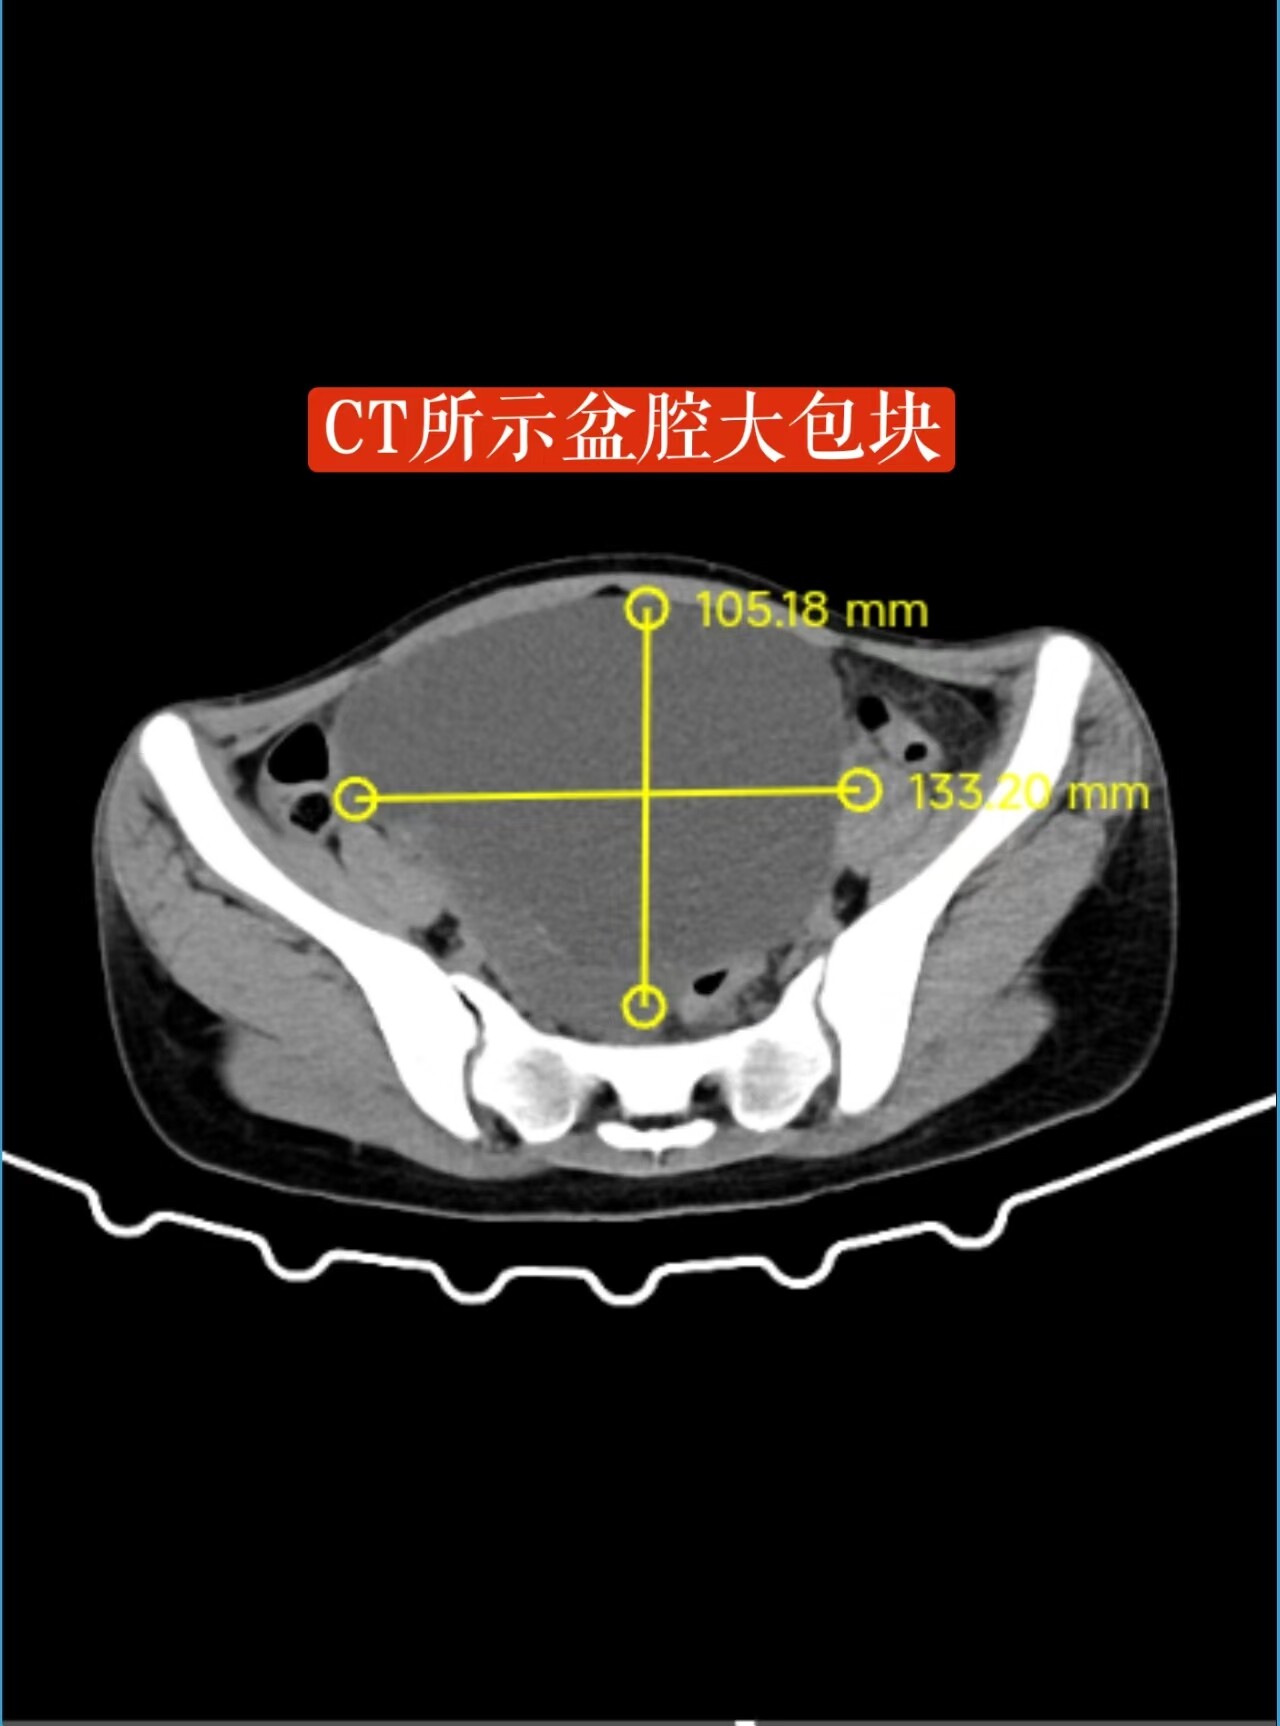

18岁的小婷(化名)是一名热爱跳舞的学生,最近因腹胀到医院检查,发现盆腔内长了一个如“皮球”大小的卵巢囊肿。面对手术,她和家人满怀担忧:手术会不会影响未来的生育?会不会留下疤痕,影响她跳舞时的形象?

了解到小婷的特殊情况后,永兴县人民医院妇科团队为她量身定制了单孔腹腔镜卵巢囊肿剥除术。手术仅通过肚脐处一个约2厘米的隐蔽切口进行,既完整剥除了囊肿,又最大限度地保护了正常的卵巢组织。术后,小婷恢复迅速,腹部几乎看不出疤痕,很快便重返校园和心爱的舞蹈课堂。